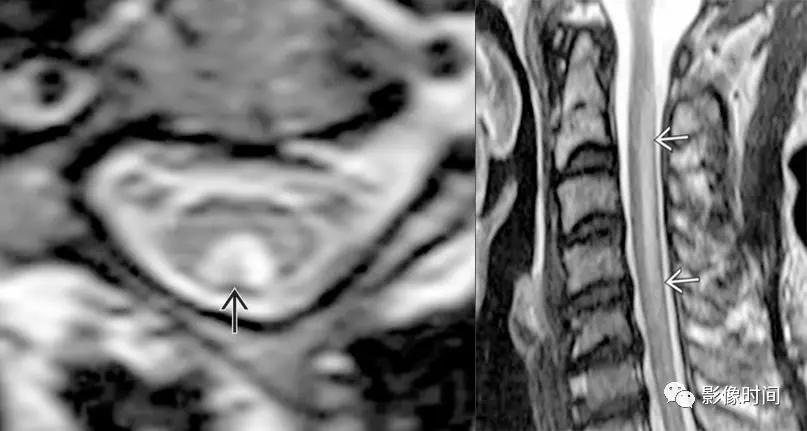

脊髓灰质炎(poliomyelitis):是由脊髓灰质炎病毒引起的脊髓前角运动神经元损害为主,患者多为 1-6 岁儿童。

MRI:

-

双侧灰质前角对称性 T2WI 高信号,类似于脊髓前动脉梗死的「鹰眼征」

急性期明显强化

T2WI双侧灰质前角对称结节状高信号,似「鹰眼」